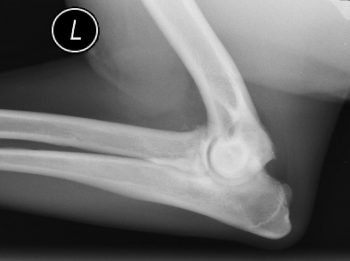

Radiography is useful for confirming presence of OA. It may give an indication as to the severity of the whole pathological picture. However, it is a poor correlator with the clinical picture, prompting the maxim: “Always treat the animal, not the radiograph.” By the time radiographic changes to the bones are present, significant and irreparable damage to the articular cartilage will have occurred (Figure 2).